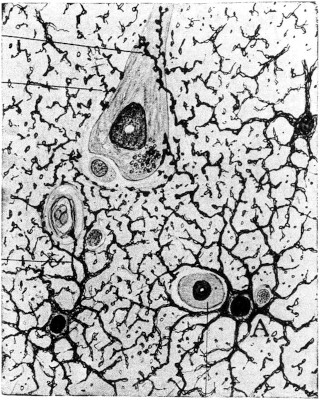

Instrumentos utilizados por Maestre de San Juan para sus estudios micrográficos. Grabados de su tratado de histología (1872): 1, microscopio mediano de Nachet; 2, mesa para trabajos micrográficos; 3, jeringa y cánulas de Ordóñez; 4, microtomo Nachet; 5, microscopio químico de L. Smith; 6, cuchillo de Strauss y 7, cuchillo doble de Valentín. Con instrumentos semejantes a estos comenzó Cajal su labor histológica.

En sus memorias, Cajal se refiere a la impresión que le produjo su primera estancia en el laboratorio de Maestre en los siguientes términos: «Sugestionado por algunas bellas preparaciones micrográficas que el doctor Maestre de San Juan y sus ayudantes (el doctor López García entre otros) tuvieron la bondad de mostrarme, y .deseoso por otra parte de aprender lo mejor posible la anatomía general, complemento indispensable de la descriptiva, resolví, a mi regreso a Zaragoza, crearme un laboratorio micrográfico». [58] Fue el primer contacto de Cajal con el ambiente de los cultivadores españoles de los estudios histológicos, que no había podido conocer hasta entonces debido a la condición marginal de la escuela médica en la que se había formado. La mitificación de su figura por parte de una abundante literatura panegírica ha insistido, como sabemos, en presentarlo poco menos que como iniciador de la micrografía en España. Ello significa desconocer la notable tradición de la indagación microscópica en nuestro país y, en concreto, la labor que en este terreno desarrollaron médicos y biólogos españoles de la generación anterior a la suya. Para situar correctamente el inicio de la dedicación de Cajal a la histología en el contexto de la actividad científica española de su tiempo, parece conveniente recordar a grandes rasgos dicha realidad histórica.